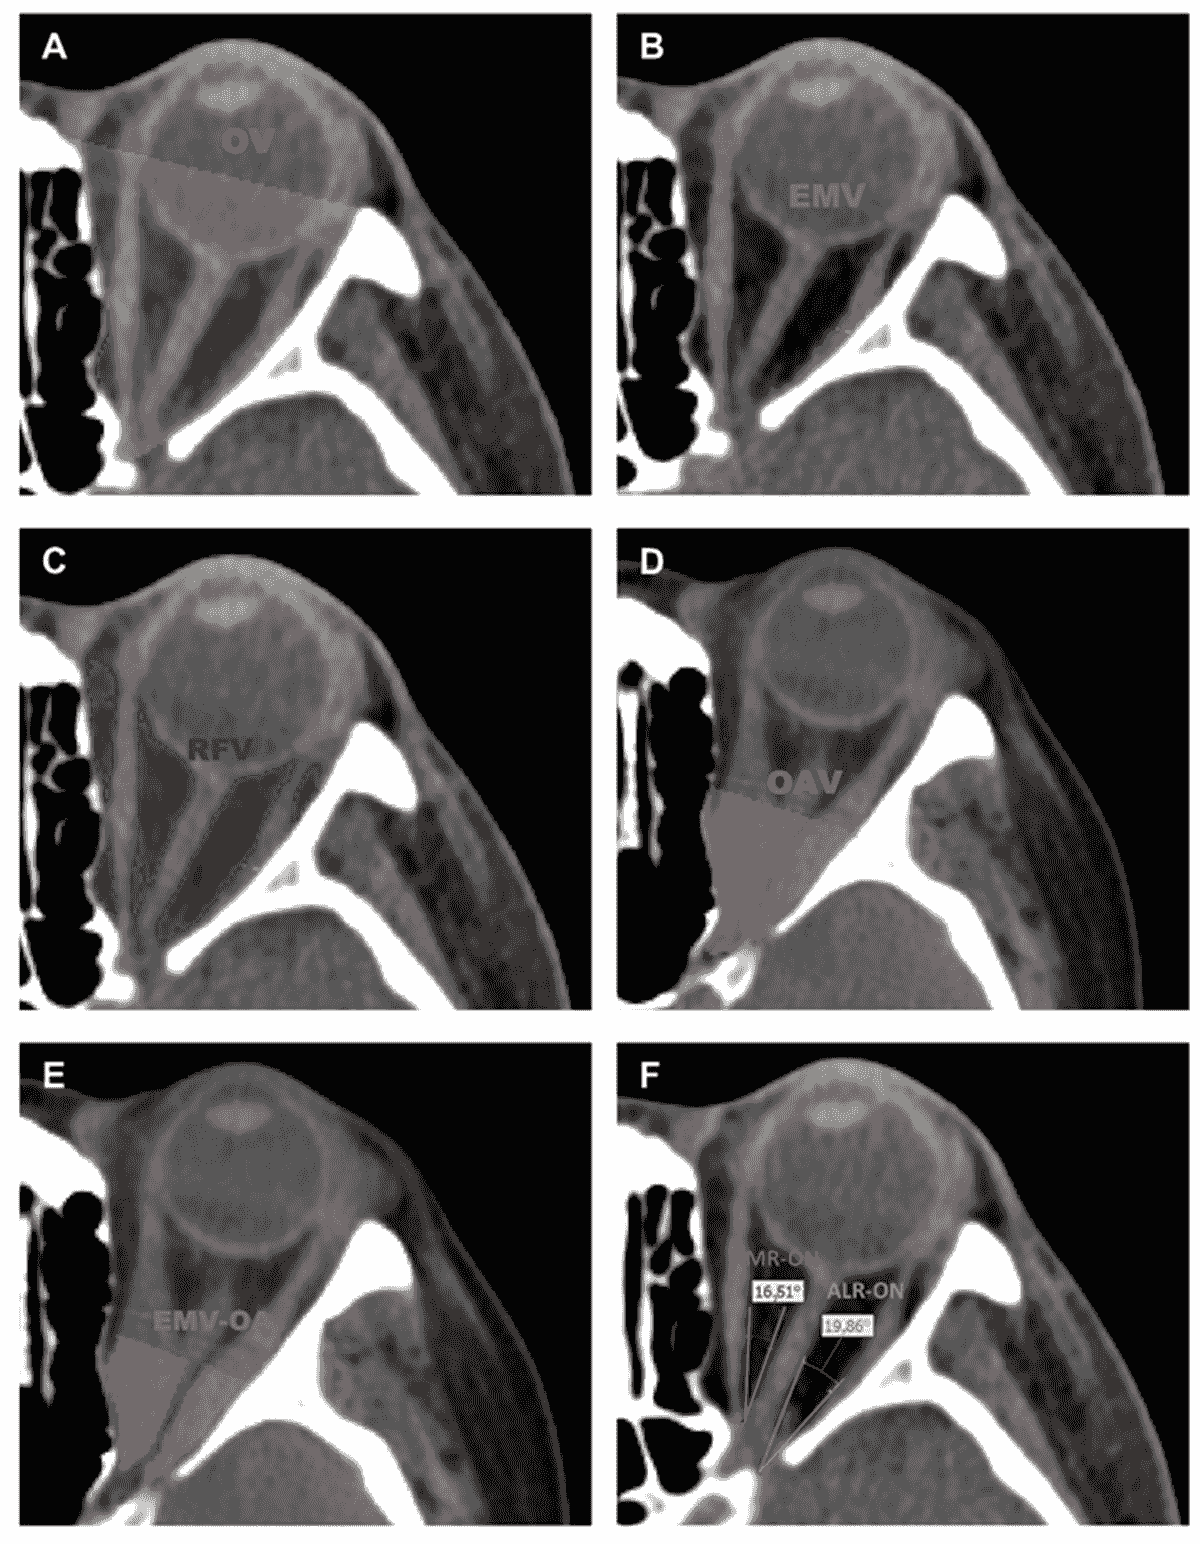

Parameter measurements include orbital volume (OV), extraocular muscle volume (EMV), retroorbital fat volume (RFV), orbital apex volume (OAV), extraocular muscle volume in orbital apex (EMV-OA), the angles between medial rectus and optic nerve (AMR-ON), and the angle between the lateral rectus and optic nerve (ALR-ON) . The extraocular muscles include four muscles as follows: medial rectus, lateral rectus, superior rectus, and inferior rectus.

Axial CT slices with the highlighted segmented tissues. (A) orbital volume (OV), (B) extraocular muscle volume (EMV), (C) retroorbital fat volume (RFV), (D) orbital apex volume (OAV), (E) extraocular muscle volume in orbital apex (EMV-OA), (F) the angle between the medial rectus and optic nerve (AMR-ON), and the angle between the lateral rectus and optic nerve (ALR-ON).